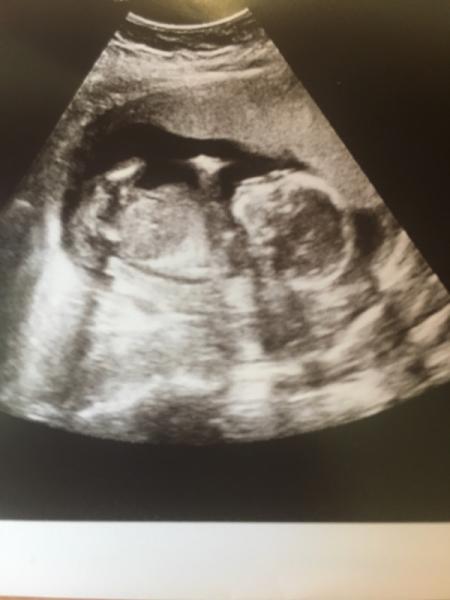

Mein Mann (und zugegebermaĂen ich auch) waren zwar ein klein wenig wehmĂŒtig, weil wir gerne unseren MĂ€dchen-Namen den wir schon bei der damaligen Schwangerschaft rausgesucht haben, vergeben wollten aber es ist natĂŒrlich trotzdem schön und wir freuen uns. So kriegt unser Sohn einen kleinen Bruder  Hier auch mal zwei Fotos

Hier auch mal zwei Fotos  Ich hoffe euch geht es auch allen gut und wĂŒnsche euch schonmal ein schönes Wochenende!